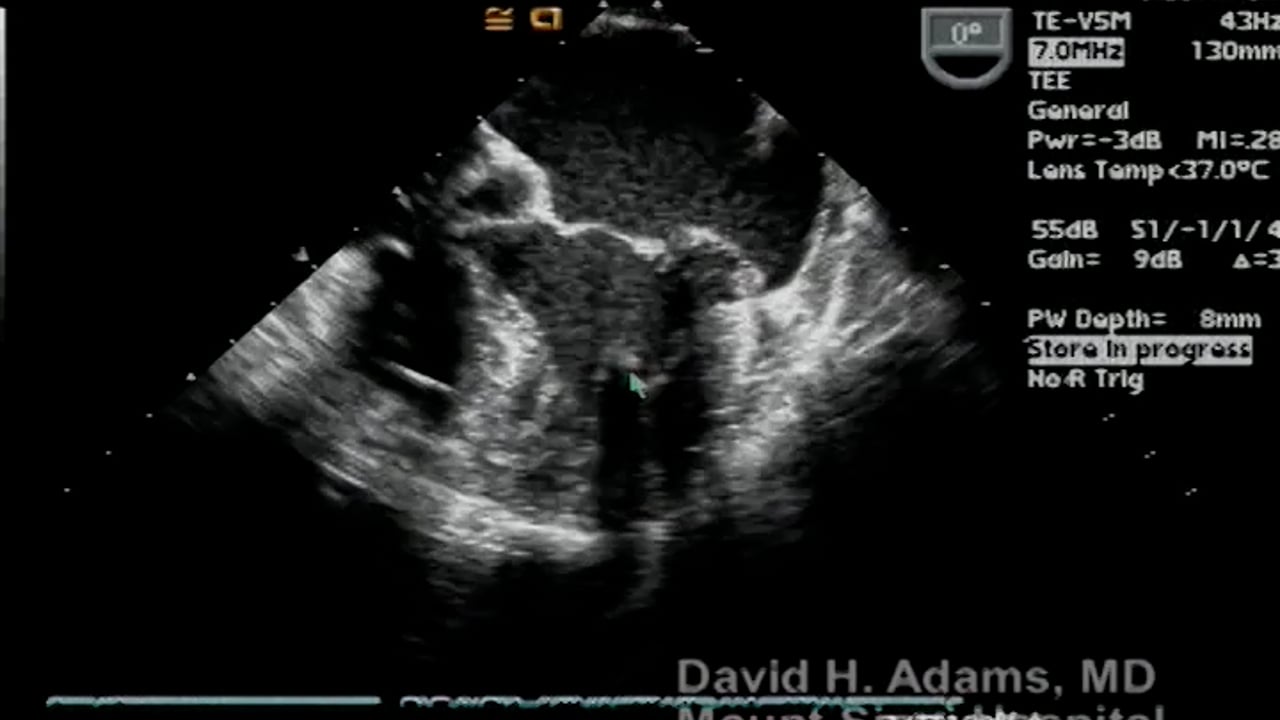

When a patient’s aortic valve is irreparably damaged, either because it has calcified and narrowed (Aortic Stenosis) or because it is leaking (Aortic Regurgitation), one proven therapy is the Ross procedure.